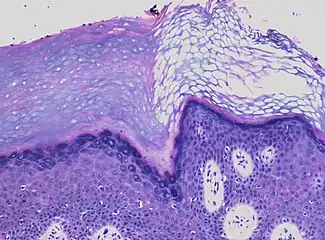

In contrast, hyperkeratosis (pictured) may also show a heterogeneous stratum corneum, but a preserved granular layer is seen.